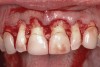

Following anesthesia, a scalloped incision was made on the keratinized tissue (Figure 3). In the interproximal area, a papilla-sparing incision was made. A full-thickness flap was raised to give access to the underlying bone (Figure 4). Both osteoplasty and ostectomy were performed to position the bone crest approximately 2 mm to 3 mm from the CEJ (Figure 5). The gingival tissue was repositioned, coinciding with the initial labial incision and the interproximal papilla. Interrupted sutures were placed (Figure 6), which were removed 7 days following the surgery.

Fig 3. Initial parasulcular scalloped incisions.

Figure 3